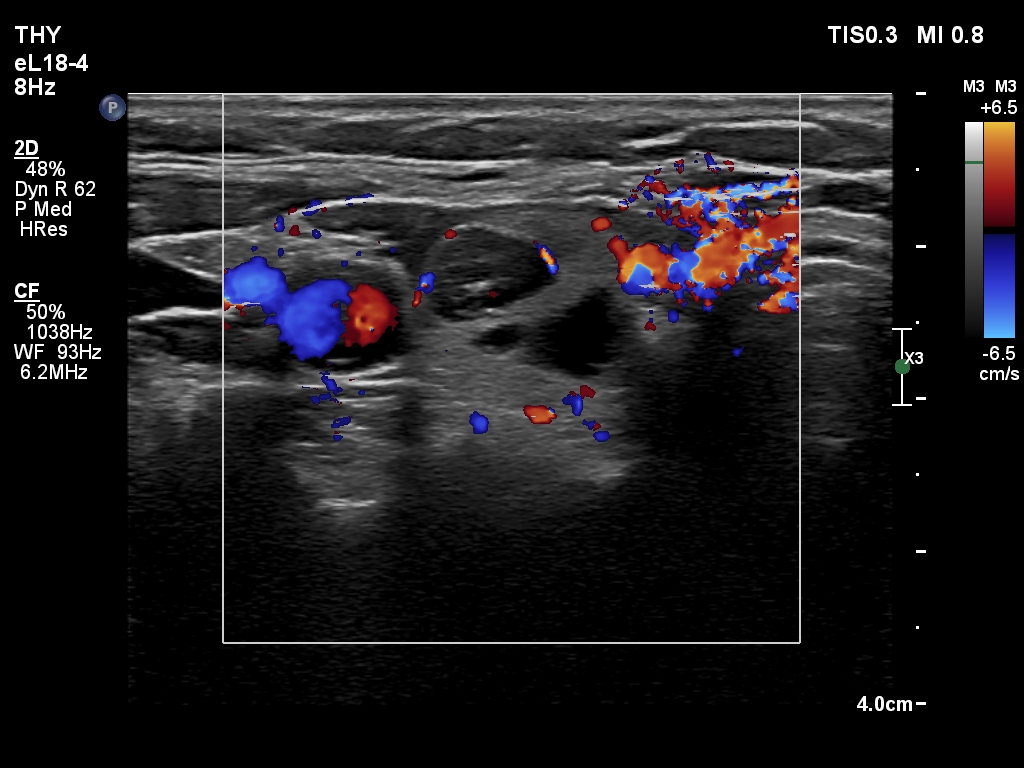

Ultrasonography. The thyroid was echonormal and had multiple nodules. There were cystic areas, an almost completely cystic nodule, and a dominantly solid nodule in the right lobe. The left lobe had three lesions. The upper solid lesion was the one we treated 16 years ago. The middle lesion was a dominantly solid while the lower one seemed to be a pure cyst. The dimensions of the nodule which has been treated with sclerotherapy were 10x11x13 mm (width, depth and length, respectively). There was a large cystic nodule in the upper pole of the left lobe. The lesion showed relatively large hyperechogenic granules. There were multiple enlarged lymph nodes lateral to the left lobe, two of largest were cystic.